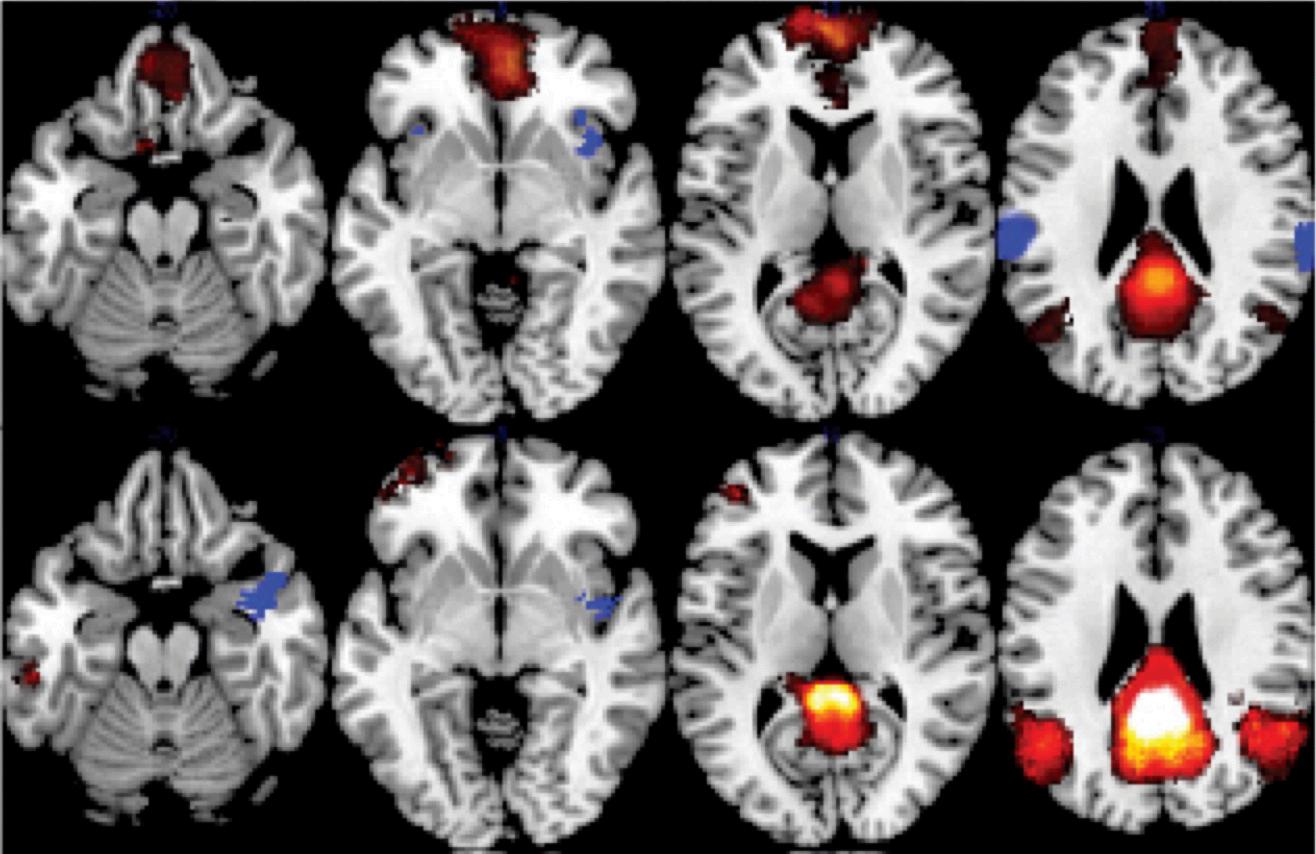

The usage of neuroplasticity is prevalent in the medical industry nowadays; it is used in stroke rehabilitation, mitigating neurodegenerative diseases, and in mental health treatment After a stroke–a loss of blood flow to part of the brain which damages one ’ s brain tissue–consistent longterm care is required for the patient’s swift recovery. Neuroplasticity harnesses the patient’s recovery process According to Physiopedia, neuroplasticity aids stroke rehabilitation by allowing healthy brain portions to recover for damaged areas by developing novel functions through processes like inter-hemispheric lateralization, formation of new connections in cortical regions, and reorganization of cortical representational maps. Furthermore, these are instinctive processes that assist such significant spontaneous recovery. Utilizing positron emission tomography (PET) and functional magnetic resonance imaging (fMRI)I–noninvasive imaging techniques–also helps people discover the latent phenomena of neuroplasticity. Patients who are suffering from neurodegenerative diseases–diseases resulting from neuron loss, representatively Alzheimer's and Parkinson's disease–can ameliorate their conditions via utilizing neuroplasticity. In accordance with BMC, neuroplasticity helps Alzheimer's and Parkinson's patients by potentially enhancing the function of brains and decelerating the speed of the disease’s progression Currently, neurologists are working on developing brain stimulation techniques that aim to mobilize neuroplasticity’s ability for essentially executing treatment by using deep brain stimulation (DBS) and transcranial magnetic stimulation (TMS)–the specific regions of the brain. What is more, even mental health problems can be coped with neuroplasticity As stated by Life Stance Health, through intentional practices involving neuroplasticity, people can fortify positive thoughts and maneuvers while weakening negative ones. Specifically, people with depression problems can train their brains to wrestle with self-activated negative thoughts, and foster selflove. Furthermore, Cognitive Behavioral Therapy (CBT) provides methods to reconstruct thought processing Also, regular exercise increases neuroplasticity and promotes cognitive function and mood regulation To sum up, neuroplasticity is widespread throughout diverse aspects of the medical system and deeply embedded into our lives. Aside from the particular pathways to strengthen people’s neuroplasticity, methods such as neurofeedback and brain-computer interfaces are also obliging to such processes.

Furthermore, Doctors at Boston Children’s Hospital concluded that greater exposure to screens from a younger age causes slower-frequency brain waves to become stronger as shown in Figure 2, which results in a state of lower awareness of surroundings and inattention When these children reach school ages, they face difficulties with focusing and struggle with cognitive control. Although other factors are involved, excessive screen time plays the biggest role in reduced executive functioning.